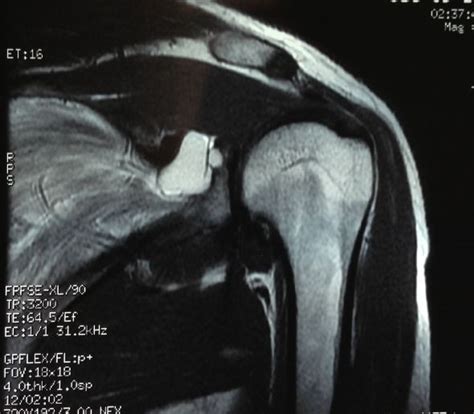

髋关节MR能检查出什么病

结合体征及专科体检,密切观察病情,股骨头早期坏死,影像学表现不典型,还有要是有长期服用激素药物或者酗酒的话,应该警惕这些表现。

髋关节mri片,专业的进

1、黑点一是片子本身不干净或是股骨头内的血管窦,不是病变引起的。

2、没有股骨头坏死的表现。最起码现在绝对不是股骨头坏死。

3、双髋关节少量积液属于正常现象,正常关节内都或有关节液的起润滑作用。不需要治疗。因为是正常的,所以不写到诊断印象中。